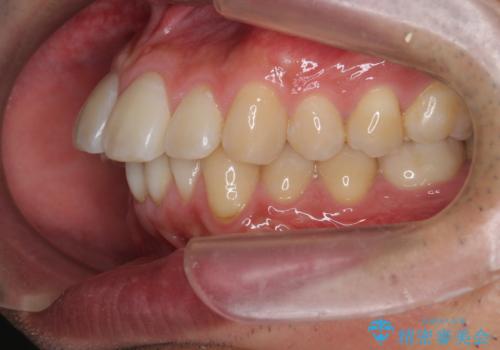

マウスピース矯正で前歯の角度、ガタガタをきれいに

- 突き出た前歯の角度、歯ブラシのしづらい前歯のがたつきの改善を希望され来院されました。

4本の小臼歯を抜きワイヤー矯正治療、下顎前歯を1本抜去しマウスピース治療のメリットデメリットを検討・相談し、より歯を抜く本数の少ないマウスピース矯正を行うこととなりました。

下顎の前歯は1本だけ抜去せざるをえませんでしたが、4本の小臼歯抜去とマルチブラケット矯正を回避することができ、治療結果・過程に満足いただくことができました。